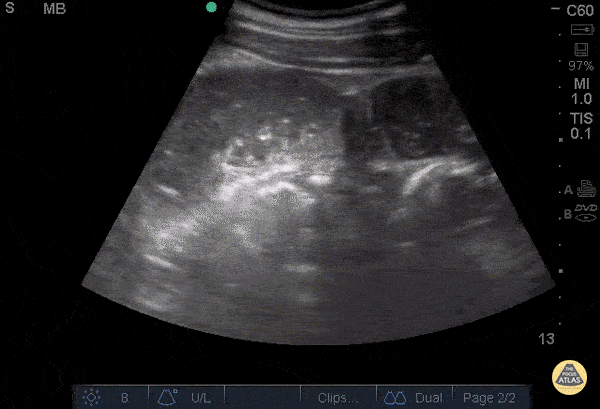

67 y/o M with PMH colon cancer s/p resection and colostomy, multiple SBO managed conservatively p/w no colostomy output for 3 days and increasing abdominal distention. POCUS shows fluid-filled, noncompressible small bowel loops dilated >2.5 cm, the most sensitive finding for POCUS diagnosis of SBO. You also see characteristic to-and-fro motion of the bowel contents. You do not see signs of severe obstruction such as extraluminal free fluid, no peristalsis, or bowel wall thickening >3 mm. Recent studies report a very high positive likelihood ratio for POCUS: 9.55 for clinical US, compared to 1.6 for radiographs, 3.6 for CT, and 6.8 for MRI. Now just convince your surgeons... Dr. Angela Cai, Dr. Kelly Maurelus - Kings County/SUNY Downstate Emergency Medicine https://www.acep.org/Content.aspx?id=100218#sm.0001bhfy70l03elmtz51w5hlmrnna